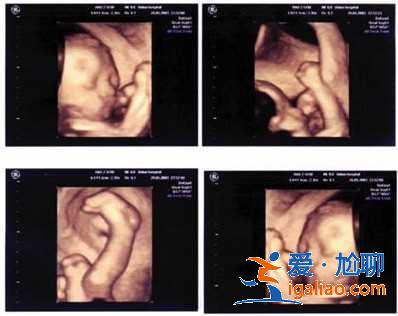

試管嬰兒技術是眾多不孕不育家庭的福音,所謂試管嬰兒,就是通過把卵子和精子都拿到體外來,讓它們在體外人工控制的環境中完成受精過程,然后把早期胚胎移植到女性的子宮中,在子宮中孕育成為孩子的技術。目前試管嬰兒技術已經推廣至全國范圍,很多朋友也想通過這樣的技術擁有自己的寶寶。